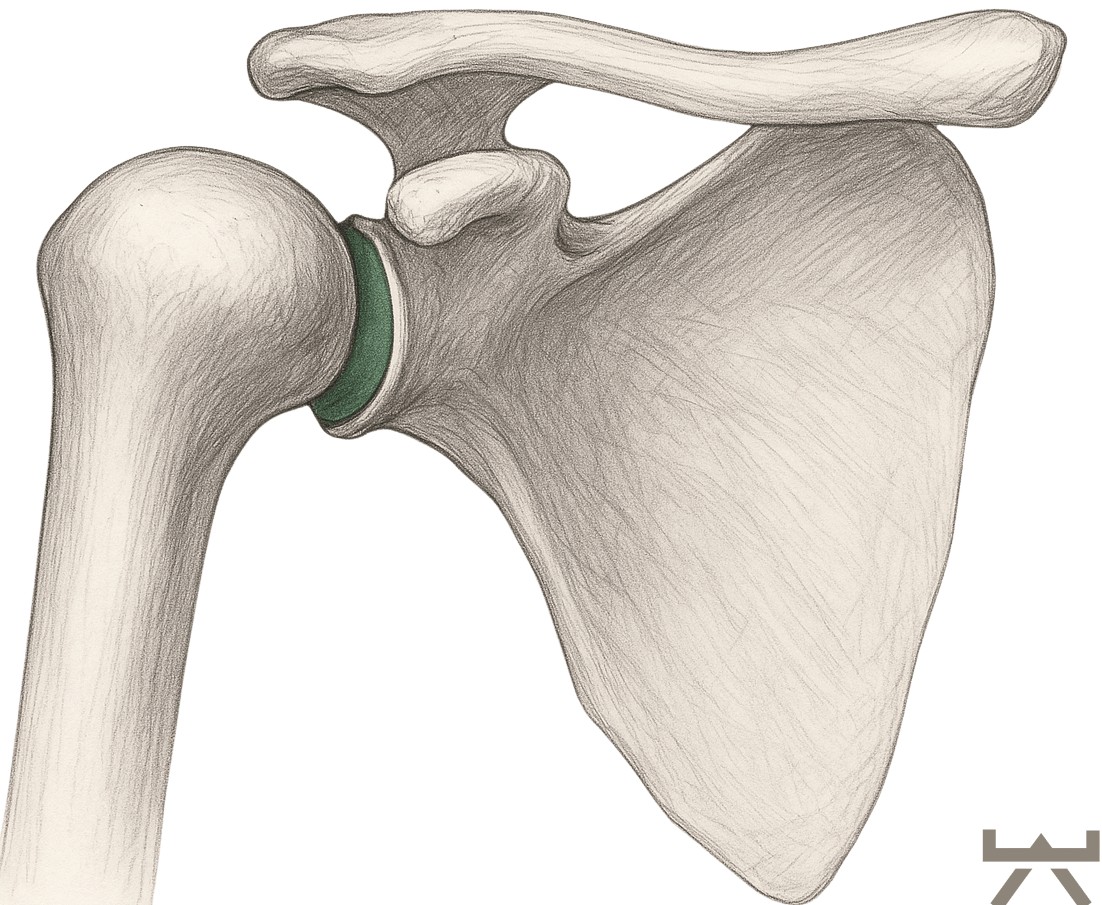

Verglichen mit der tiefen knöchernen Hüftpfanne ist die Schulterpfanne eher als kleine Schale zu bezeichnen. Diese Schale wird durch das Labrum noch verstärkt. Das Labrum ist einen Knorpelring, der direkt an der Gelenkpfanne der Schulter ansetzt. Das Labrum ist wiederum mit den Muskeln der Rotatorenmanschette verbunden, die zusammen die Schulterkapsel bilden. Sie sollten diese Muskeln als eine dynamische Gelenkpfanne betrachten, die zur Stabilisierung des Schulterkopfes beiträgt, indem sie genau im richtigen Moment angespannt wird, wenn sie ihre Bewegungen ausführen.

Für die Anforderungen, die wir an die Schulter stellen, ist ihre Anatomie sehr sinnvoll. Die minimale Gelenkpfanne ermöglicht es uns, den Arm frei in allen Richtungen zu bewegen. Durch diese Bewegungsfreiheit wird die Stabilisierung der Schulter für den Körper jedoch schwieriger.